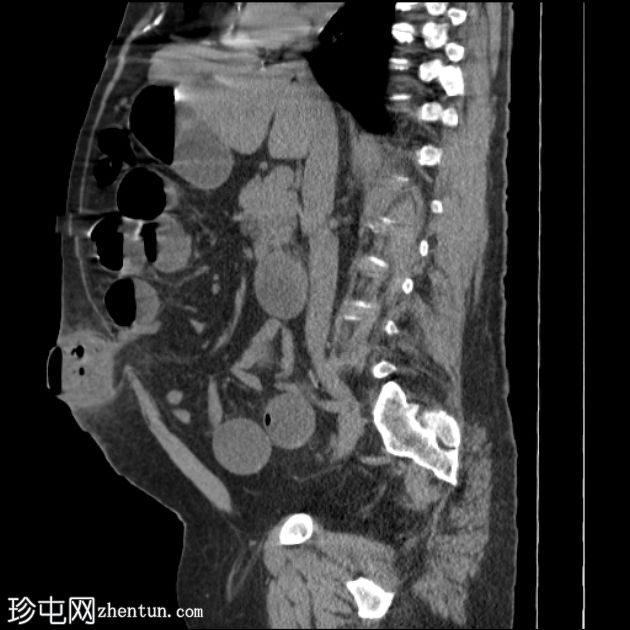

矢状位

平扫

多处扩张的小肠袢内可见多个气液平面,直至进入脐疝的肠袢处可见移行点,而从疝口出来的远端小肠袢则呈塌陷状态。

诊断:嵌顿性脐疝继发急性小肠梗阻。